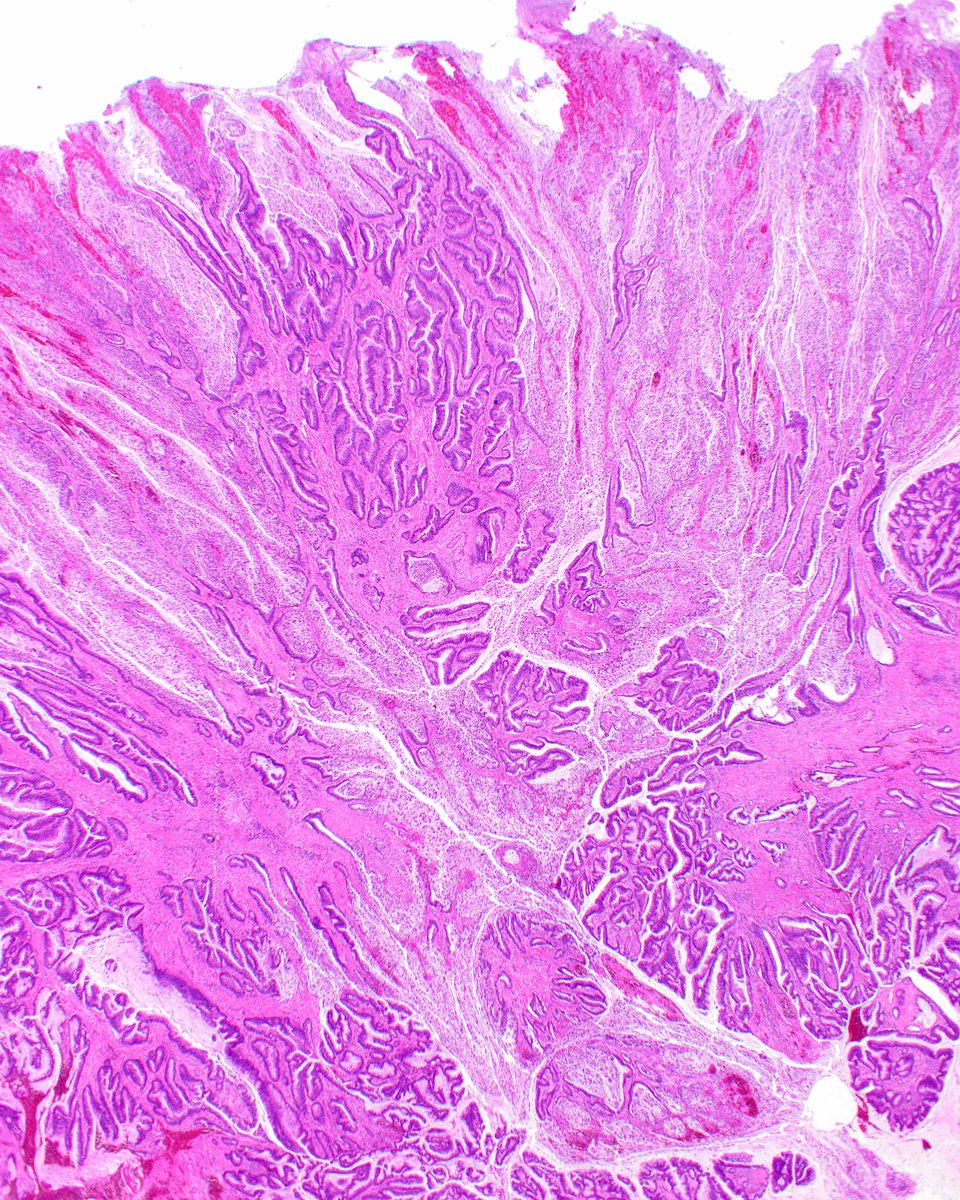

Signet ring cell change in an eroded tubulovillous adenoma. The cells in question are degenerated sloughed cells in the gland lumina. The are not carcinoma. https://t.co/11aBMJXEmQ